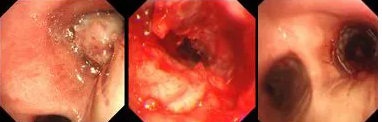

原來,秦爺爺入院時(shí)診斷為“右主支氣管”鱗狀細(xì)胞癌伴壞死。他的右主支氣管被腫瘤完全堵塞,混合性狹窄。面罩吸氧10升/分的狀況下,指脈氧只有85%,無法平躺,呼吸困難,病情十分危急,隨時(shí)有生命危險(xiǎn)。

經(jīng)評估并與家屬溝通同意后,歐陽海峰副院長決定為患者實(shí)施TTS氣道支架手術(shù)。手術(shù)當(dāng)天,在麻醉手術(shù)中心的配合下,歐陽海峰副院長為患者在局麻下快速凍切腫瘤組織,實(shí)現(xiàn)右主支氣管再通,并經(jīng)氣管鏡活檢孔道迅速植入14*30 TTS支架一枚。支架植入過程耗時(shí)僅6秒,迅速緩解了患者的氣短瀕死癥狀。